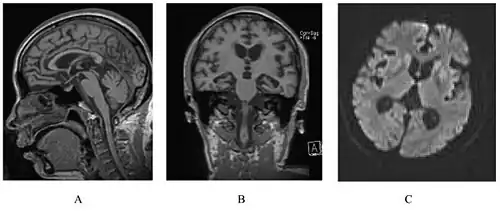

| A person with inherited prion disease has cerebellar atrophy. This is quite typical of GSS. | |